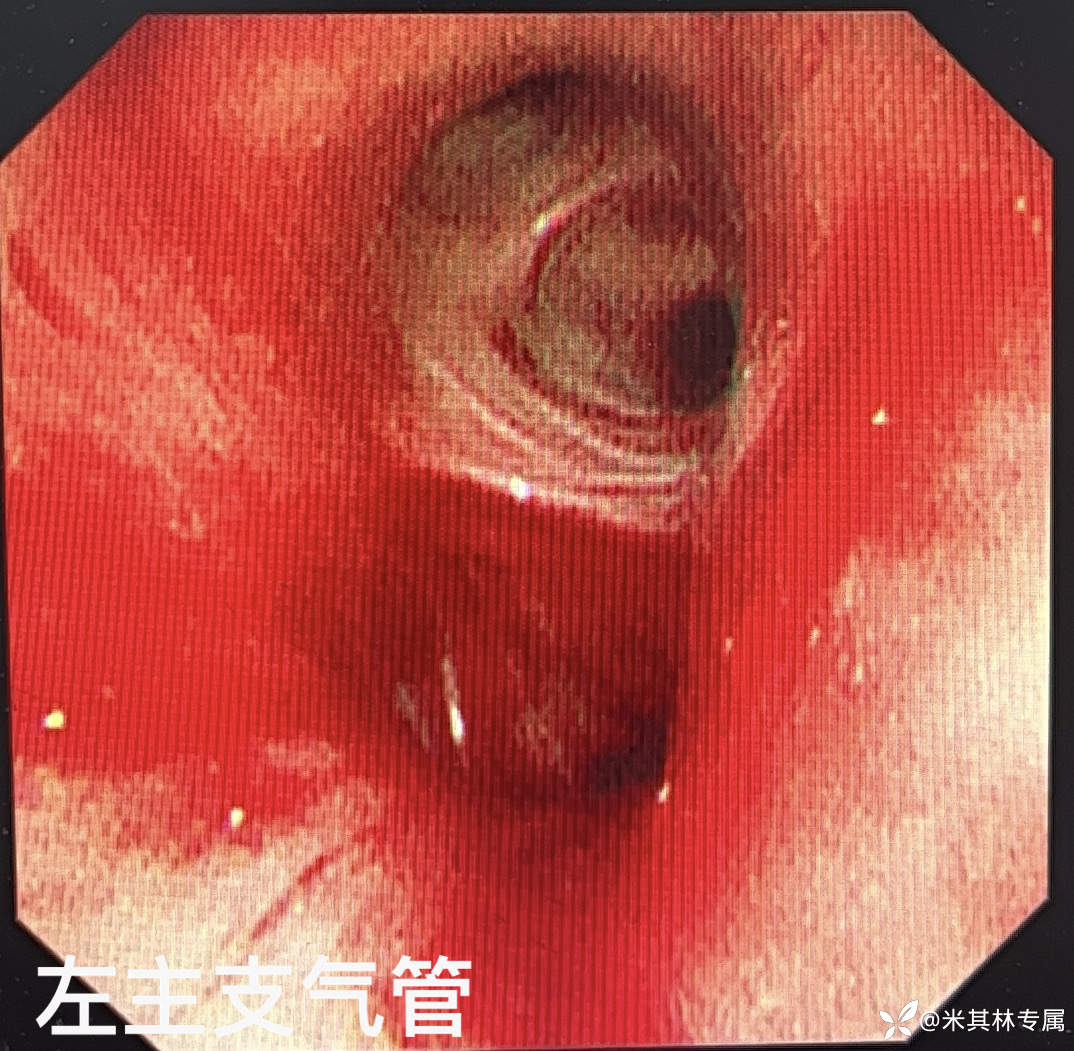

今日气管镜检查:

病变描述:

声带:开闭良好

气管:气管管腔通畅,软骨环清晰,粘膜光滑。隆突:锐利。

左侧:左侧主支气管、左下叶基底段可见少许血迹附着左肺下叶内前基底段可见少许血液溢出,余各段支气管管腔通畅,粘膜光滑。

右侧:各段支气管管腔通畅,粘膜光滑。